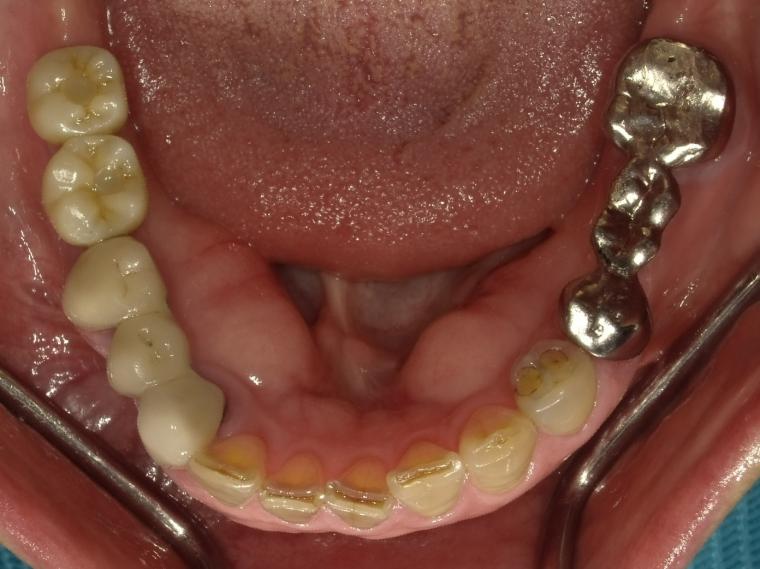

AFTER

74歳女性

/上下3本/インプラント埋込手術

【治療内容】

現在も定期検診で拝見しております。

【費用】

140万円

【治療期間】

11ヶ月